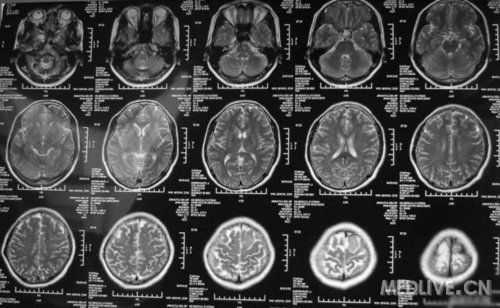

患者女,56岁,因右侧肢体活动不利2天于2011-06-15入院。查体:神志清,精神可,右侧肢体肌力4级,余无阳性体征。CT示左额叶占位,脑膜瘤可能性大。MRI示左额镰旁脑膜瘤,脑干左半亚急性梗塞。给予活血、神经营养、对症治疗,现一般情况好。请高手指点,何时手术切除脑膜瘤好啊?